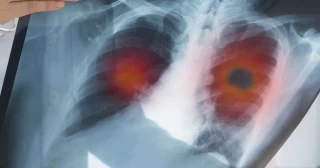

La primera vacuna contra el cáncer de pulmón se pone a prueba en Europa (también en España)

Este cáncer sigue siendo una de las principales causas de mortalidad en todo el mundo, con 1,8 millones de muertes en 2020. La empresa biotecnológica alemana BioNTech ha dado inicio a la primera prueba en humanos de la vacuna BNT116, una innovadora terapia basada en (ARNm diseñada específicamente para combatir el cáncer de pulmón no microcítico). Este ensayo clínico se lleva a cabo en 7 países, incluido España, con el objetivo de evaluar la seguridad y eficacia de la vacuna en combinación con tratamientos tradicionales contra el cáncer.